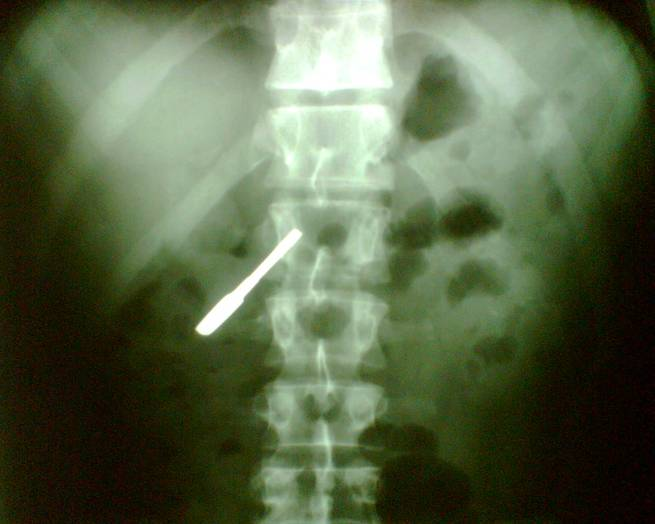

15.2.2.5. Foreign bodies

Foreign bodies could enter the human body in every possible way. The best way to detect them if we are familiar with the application fields of the imaging modalities.

With plain radiography radiopaque foreign objects could be identified. Let’s not forget that images always should be taken at least from two directions. Plain radiographs contain summation images of one projection in order to be able to localize the object orthogonal projections are necessary, fluoroscopy and CT can also be helpful in undetermined cases.

12 A young dancer was partying in the dressing room with his friends. He suddenly swallowed down an object which on the abdominal radiogram proved to be a cupboard key.

Non-radiopaque foreign bodies are more difficult to detect, superficially located objects (e.g. impacted sutures) could be identified by US, deeper located object can be looked up with MRI.